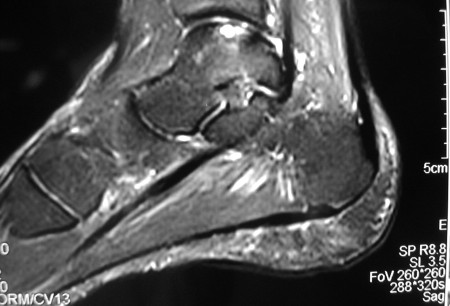

Sagittal magnetic resonance image (MRI) of the talus, showing an osteochondral lesion on the posterior aspect of the talar dome

Gupta RK, Kansay R, Aggarwal V, et al. Osteochondritis dessicans of the talus in a 26-year-old woman. BMJ Case Reports 2009; doi:10.1136/bcr.06.2008.0091